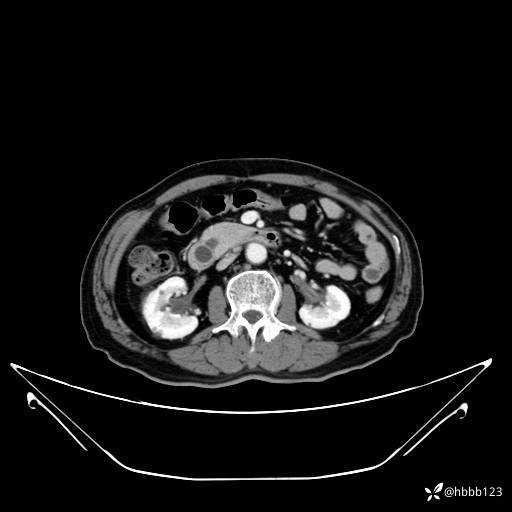

门诊完善上腹部CT平扫+增强扫描:

动脉期: